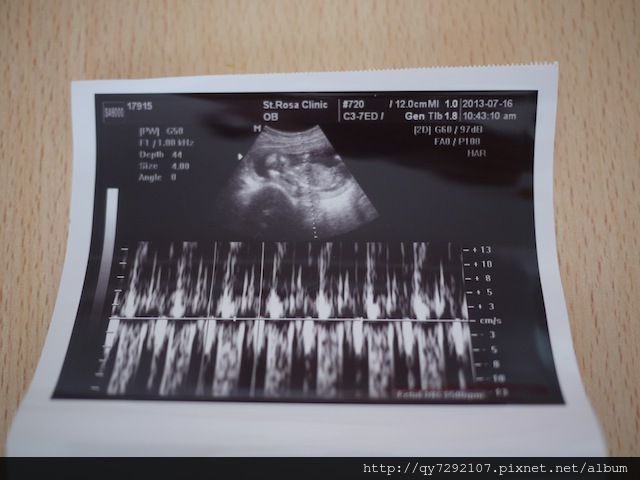

前兩天我經歷了差點失去Pony的驚魂與恐懼!上禮拜帶妹醬去未來的幼稚園參觀體驗,回家之後深感身體不適,預估自己可能是中暑了,隔天一早馬上高燒到40度,看了醫生吃了退燒藥,昏睡了一整天,隔天一樣感覺身體很虛弱,婆婆趕來幫我照顧妹醬,第二天是星期日,T先生卻要加班,我不好意思再麻煩婆婆來幫忙,獨自照顧妹醬,到了晚上就一直感覺身體很不適,半夜起來上廁所時,發現我出血了!!我全身發抖,心想:怎麼會這樣?!怎麼會出血?都已經要4個月了,應該要很穩定才是,回到床上,我搖醒T先生害怕的眼淚直流,一整個晚上宮縮不停,有好幾次我都覺得我快撐不下去了,Pony快被我不停歇地宮縮給擠出來了,我不停地禱告,祈求上帝體諒一個母親渴望孩子的心情,幫助我渡過每一次的宮縮,我不停的對Pony喊話,告訴他/她我有多麼期盼他/她的到來,希望他/她可以努力留在我體內,我隔天一早,我們直奔醫院,當醫生把超音波探頭放在我的肚皮上,我清楚的看見Pony小小的人形還有一閃一閃的心跳,我頓時安心了不少,眼眶也濕了,醫生說:baby很好很健康,我們來聽聽胎心音。聽到Pony砰!砰!砰!的胎心音時,我感動的哭了…從去年到現在,懷孕第四次,感謝妹醬平安出生之外,經歷了2次小產,我都只有經歷到前期辛苦的害喜孕吐與最後的失去失望,都沒有最後孩子抱在懷中的喜悅,這一次,終於~讓我聽到baby的心跳了!這個美妙的音樂,是給我一直不放棄擁有第二個孩子最好的鼓舞!